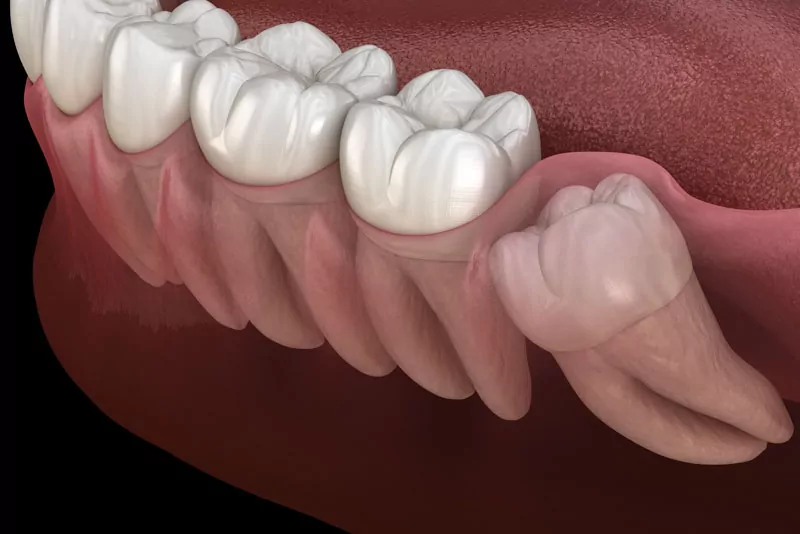

Wisdom Tooth Removal

Wisdom tooth extraction is performed when third molars are impacted or painful. Safe, quick, and usually done under local anesthesia. Prevents crowding, infection, and jaw pain. Post-surgery care ensures quick recovery. Recommended by dentists for long-term oral health.